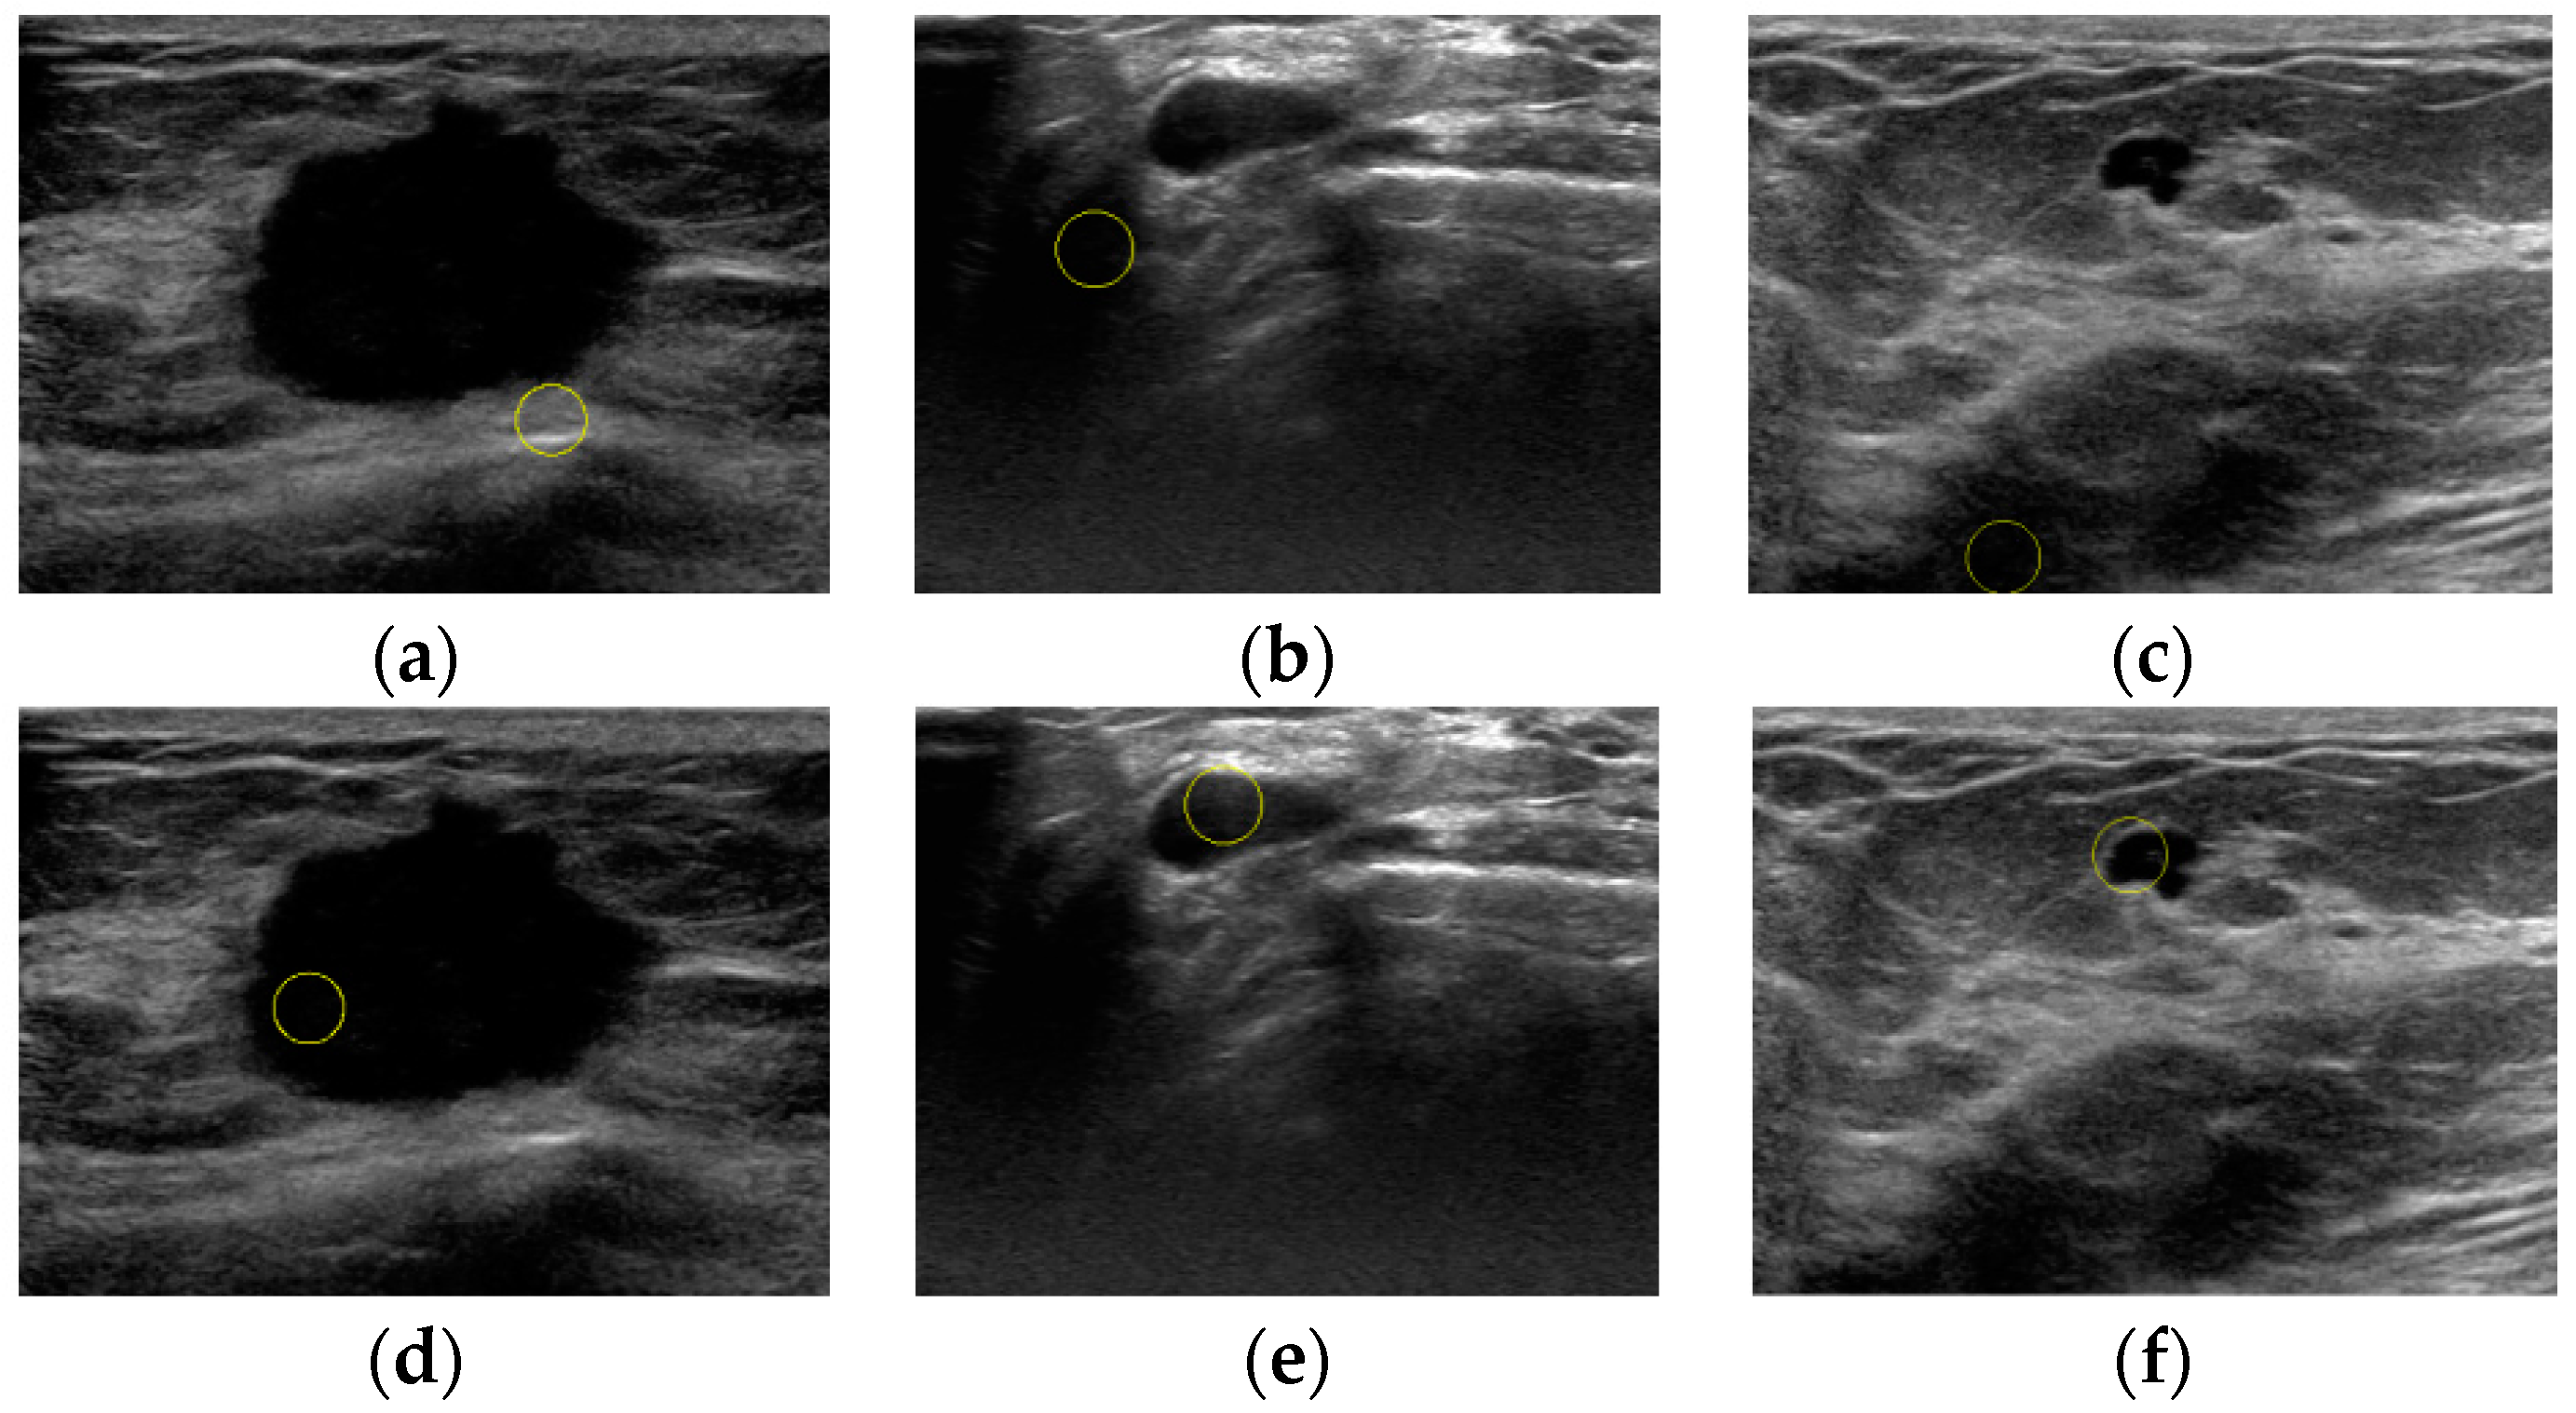

An Automatic Localization Algorithm for Ultrasound Breast Tumors Based on Human Visual Mechanism

Xie, Y.; Chen, K.; Lin, J. An Automatic Localization Algorithm for Ultrasound Breast Tumors Based on Human Visual Mechanism. Sensors 2017, 17, 1101. https://doi.org/10.3390/s17051101